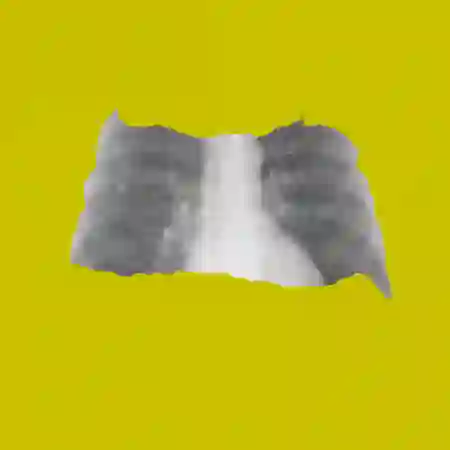

The remarkable success of deep learning has prompted interest in its application to medical imaging diagnosis. Even though state-of-the-art deep learning models have achieved human-level accuracy on the classification of different types of medical data, these models are hardly adopted in clinical workflows, mainly due to their lack of interpretability. The black-box-ness of deep learning models has raised the need for devising strategies to explain the decision process of these models, leading to the creation of the topic of eXplainable Artificial Intelligence (XAI). In this context, we provide a thorough survey of XAI applied to medical imaging diagnosis, including visual, textual, example-based and concept-based explanation methods. Moreover, this work reviews the existing medical imaging datasets and the existing metrics for evaluating the quality of the explanations. In addition, we include a performance comparison among a set of report generation-based methods. Finally, the major challenges in applying XAI to medical imaging and the future research directions on the topic are also discussed.